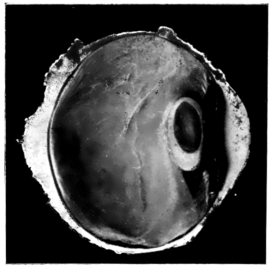

PLATE IV.

22.

LENS DISLOCATED BEHIND RETINA

curly bracket span

23.

FISTULA OF THE CORNEA

24.

CAPSULO-CORNEAL SYNECHIA

25.

RETINO-CORNEAL SYNECHIA

26.

SCLERAL FISTULA

27.

"    " (MAGNIFIED)